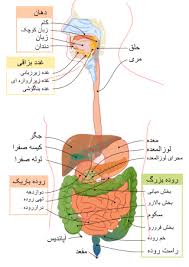

قیمت: 52٬000 تومان - دسته بندی فایل: پاورپوینتپاورپوینت پانکراس

فروش ویژه پاوزپوینت حرفه ای پانکراس با تخفیف استثنایی قیمت 63 هزار تومان تعداد اسلاید: 30 اسلاید